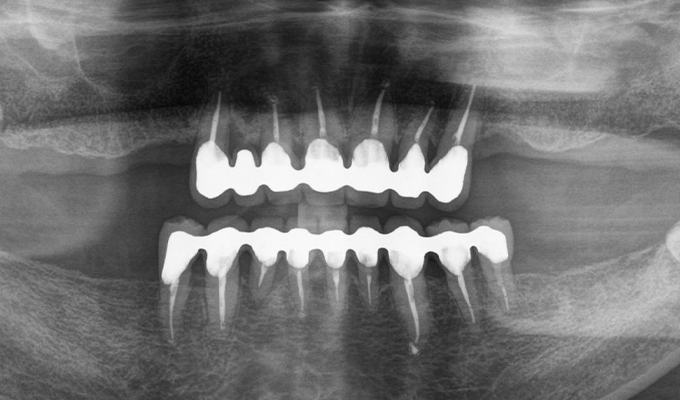

初診時(2010年)

初回メンテナンス時(2014年)

保存が難しい歯を抜歯し、上はインプラント8本、下は奥歯にインプラント4本埋入しました。

補綴は変色しないメタルボンドを選択されたので治療完了して11年経過してもとてもきれいな状態で維持されています。